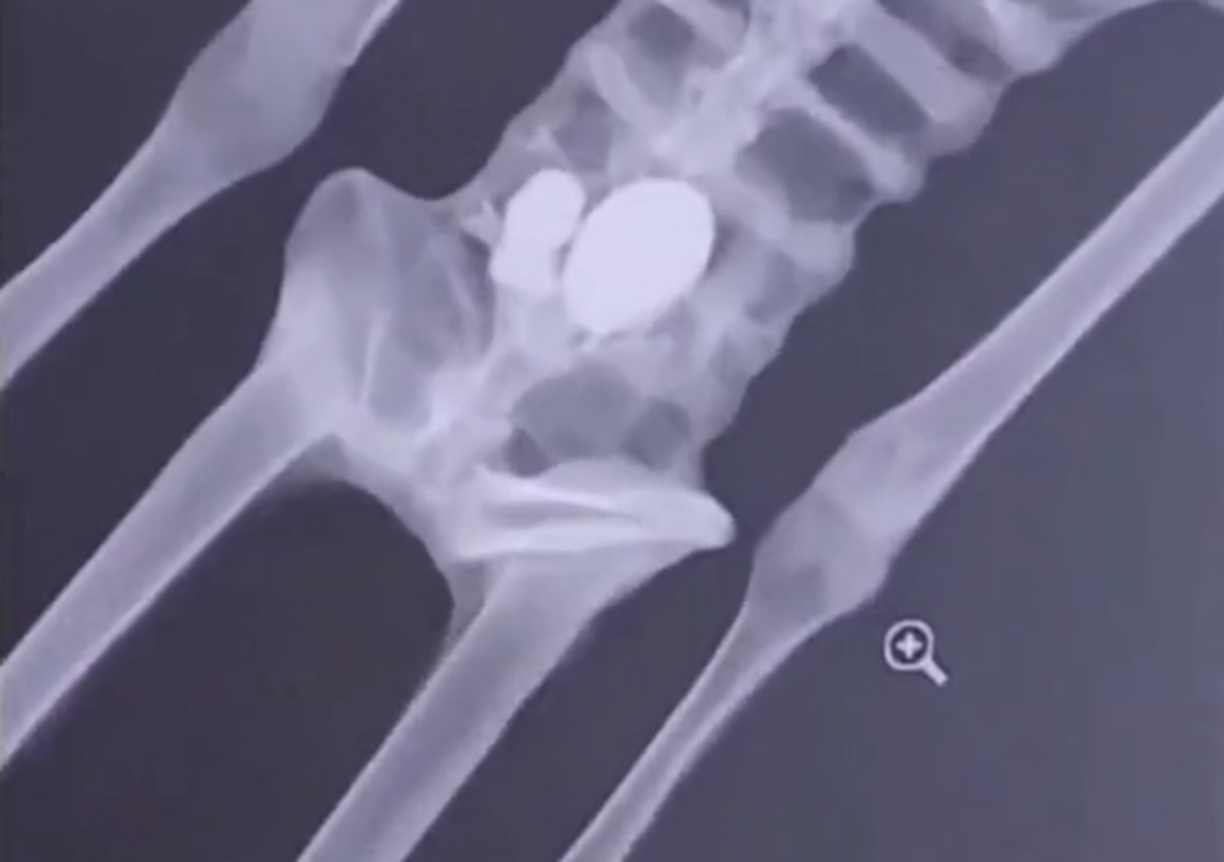

13 / 15Esto se pudo comprobar mediante pruebas de radiología, espectroscopía infrarroja, osteología comparada e histología, detalló, las cuales “revelaron que eran elementos armados con huesos de animales y huesos de humanos pegados con gomas sintéticas”. Además de que no se encontraron células, solo fibra vegetal, gomas, pegamentos y aceites.

14 / 15El experto consideró que esas muestras son iguales a las presentadas en el legislativo mexicano. “Esas cabezas que yo revisé tienen la misma estructura, composición, diseño y estilo”, aseguró.

15 / 15Destacó que “no hay armonía atómica ni lógica evolutiva” y que esos “seres” jamás hubieran podido caminar, “ni siquiera pararse con ese tipo de articulaciones planas, rotas, pegadas, mal ejecutadas”.